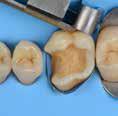

Why deep margin elevation?

Deep margin elevation will make the impression easier by moving the proximal margin of the restoration supra-gingivally, which is especially important for intra-oral scanning. It helps in avoiding periodontal surgical procedures. It makes isolation of the prepared tooth and luting of the final restoration easier.

• Isolation with rubber dam is highly recommended.

• For a better emergence profile, use Teflon tape in the space between the matrix and the adjacent tooth instead of a wedge. Do not use the same matrix as you use for creating a contact point in direct restorations.

• Selective etching of the enamel is recommended.

• Use XBW shade of G-aenial® Universal Injectable for easy differentiation between the tooth, composite material and the restoration.

• The height of the new margin should be slightly above the gingival margin (1mm).

1. Clean the tooth surfaces, rinse thoroughly and dry.

2. Apply a matrix adapted to the technique. Gingival margin of the preparation should be well sealed.

3. Etch the enamel.

5. Dry and light-cure.

6. Apply G-ænial Universal Injectable to the gingival margin of the proximal box.

7. Light cure

8. Remove the matrix and check for

4. Apply a bonding agent (G-Premio BOND or G2-BOND Universal).